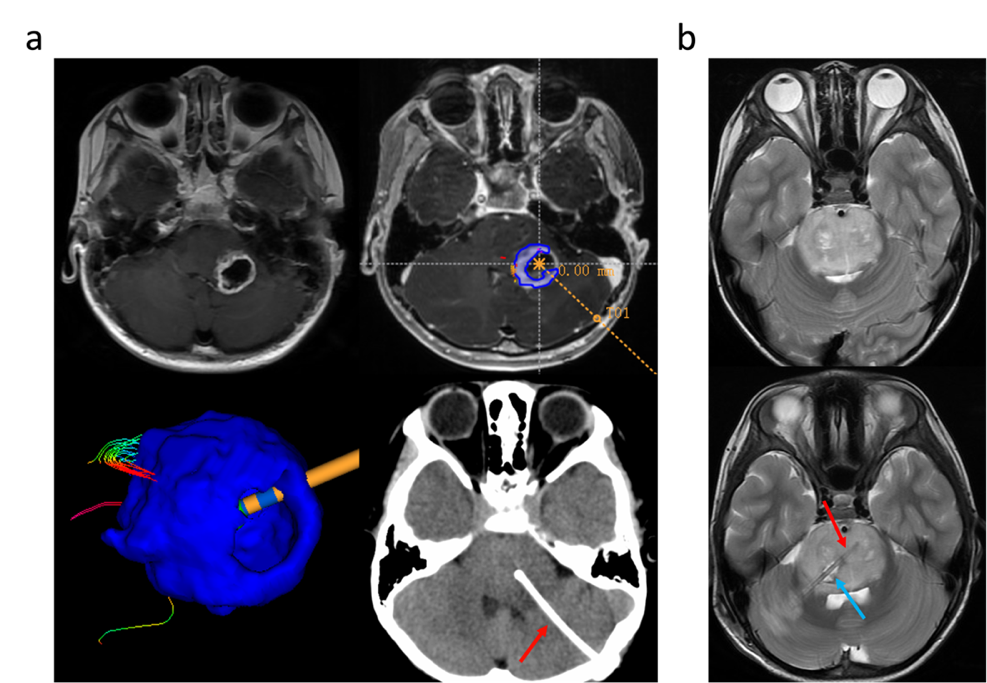

患者在入院后行头颅核磁共振检查,确定病灶的主体位置,并制定手术方案。使用REME机器人将头颅CT影像以及MRI影像进行融合,确定穿刺的路径,进行穿刺活检。活检后进行术中冰冻病理的检查,如果病理结果回报确定为高级别胶质瘤,则沿着活检通道进行Ommaya囊的植入(图1)。

图1:本图展示了Ommaya储液囊在脑干中的示意图位置以及病毒治疗后的T2磁共振代表影像